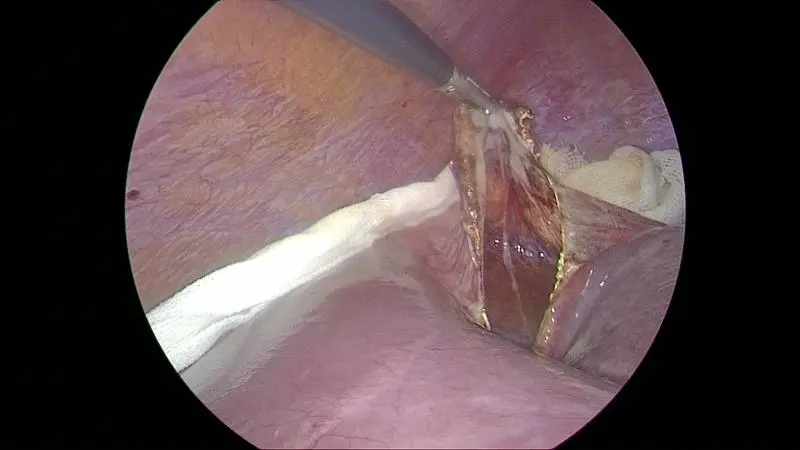

3. 引流方式: 囊肿引流方法包括穿刺引流、外科手术引流等多种方式。穿刺引流一般引流出的时间较短,可在几小时内完成;而外科手术引流则通常需要更长的时间,有时需要留置引流管几天才能全部引流出来。